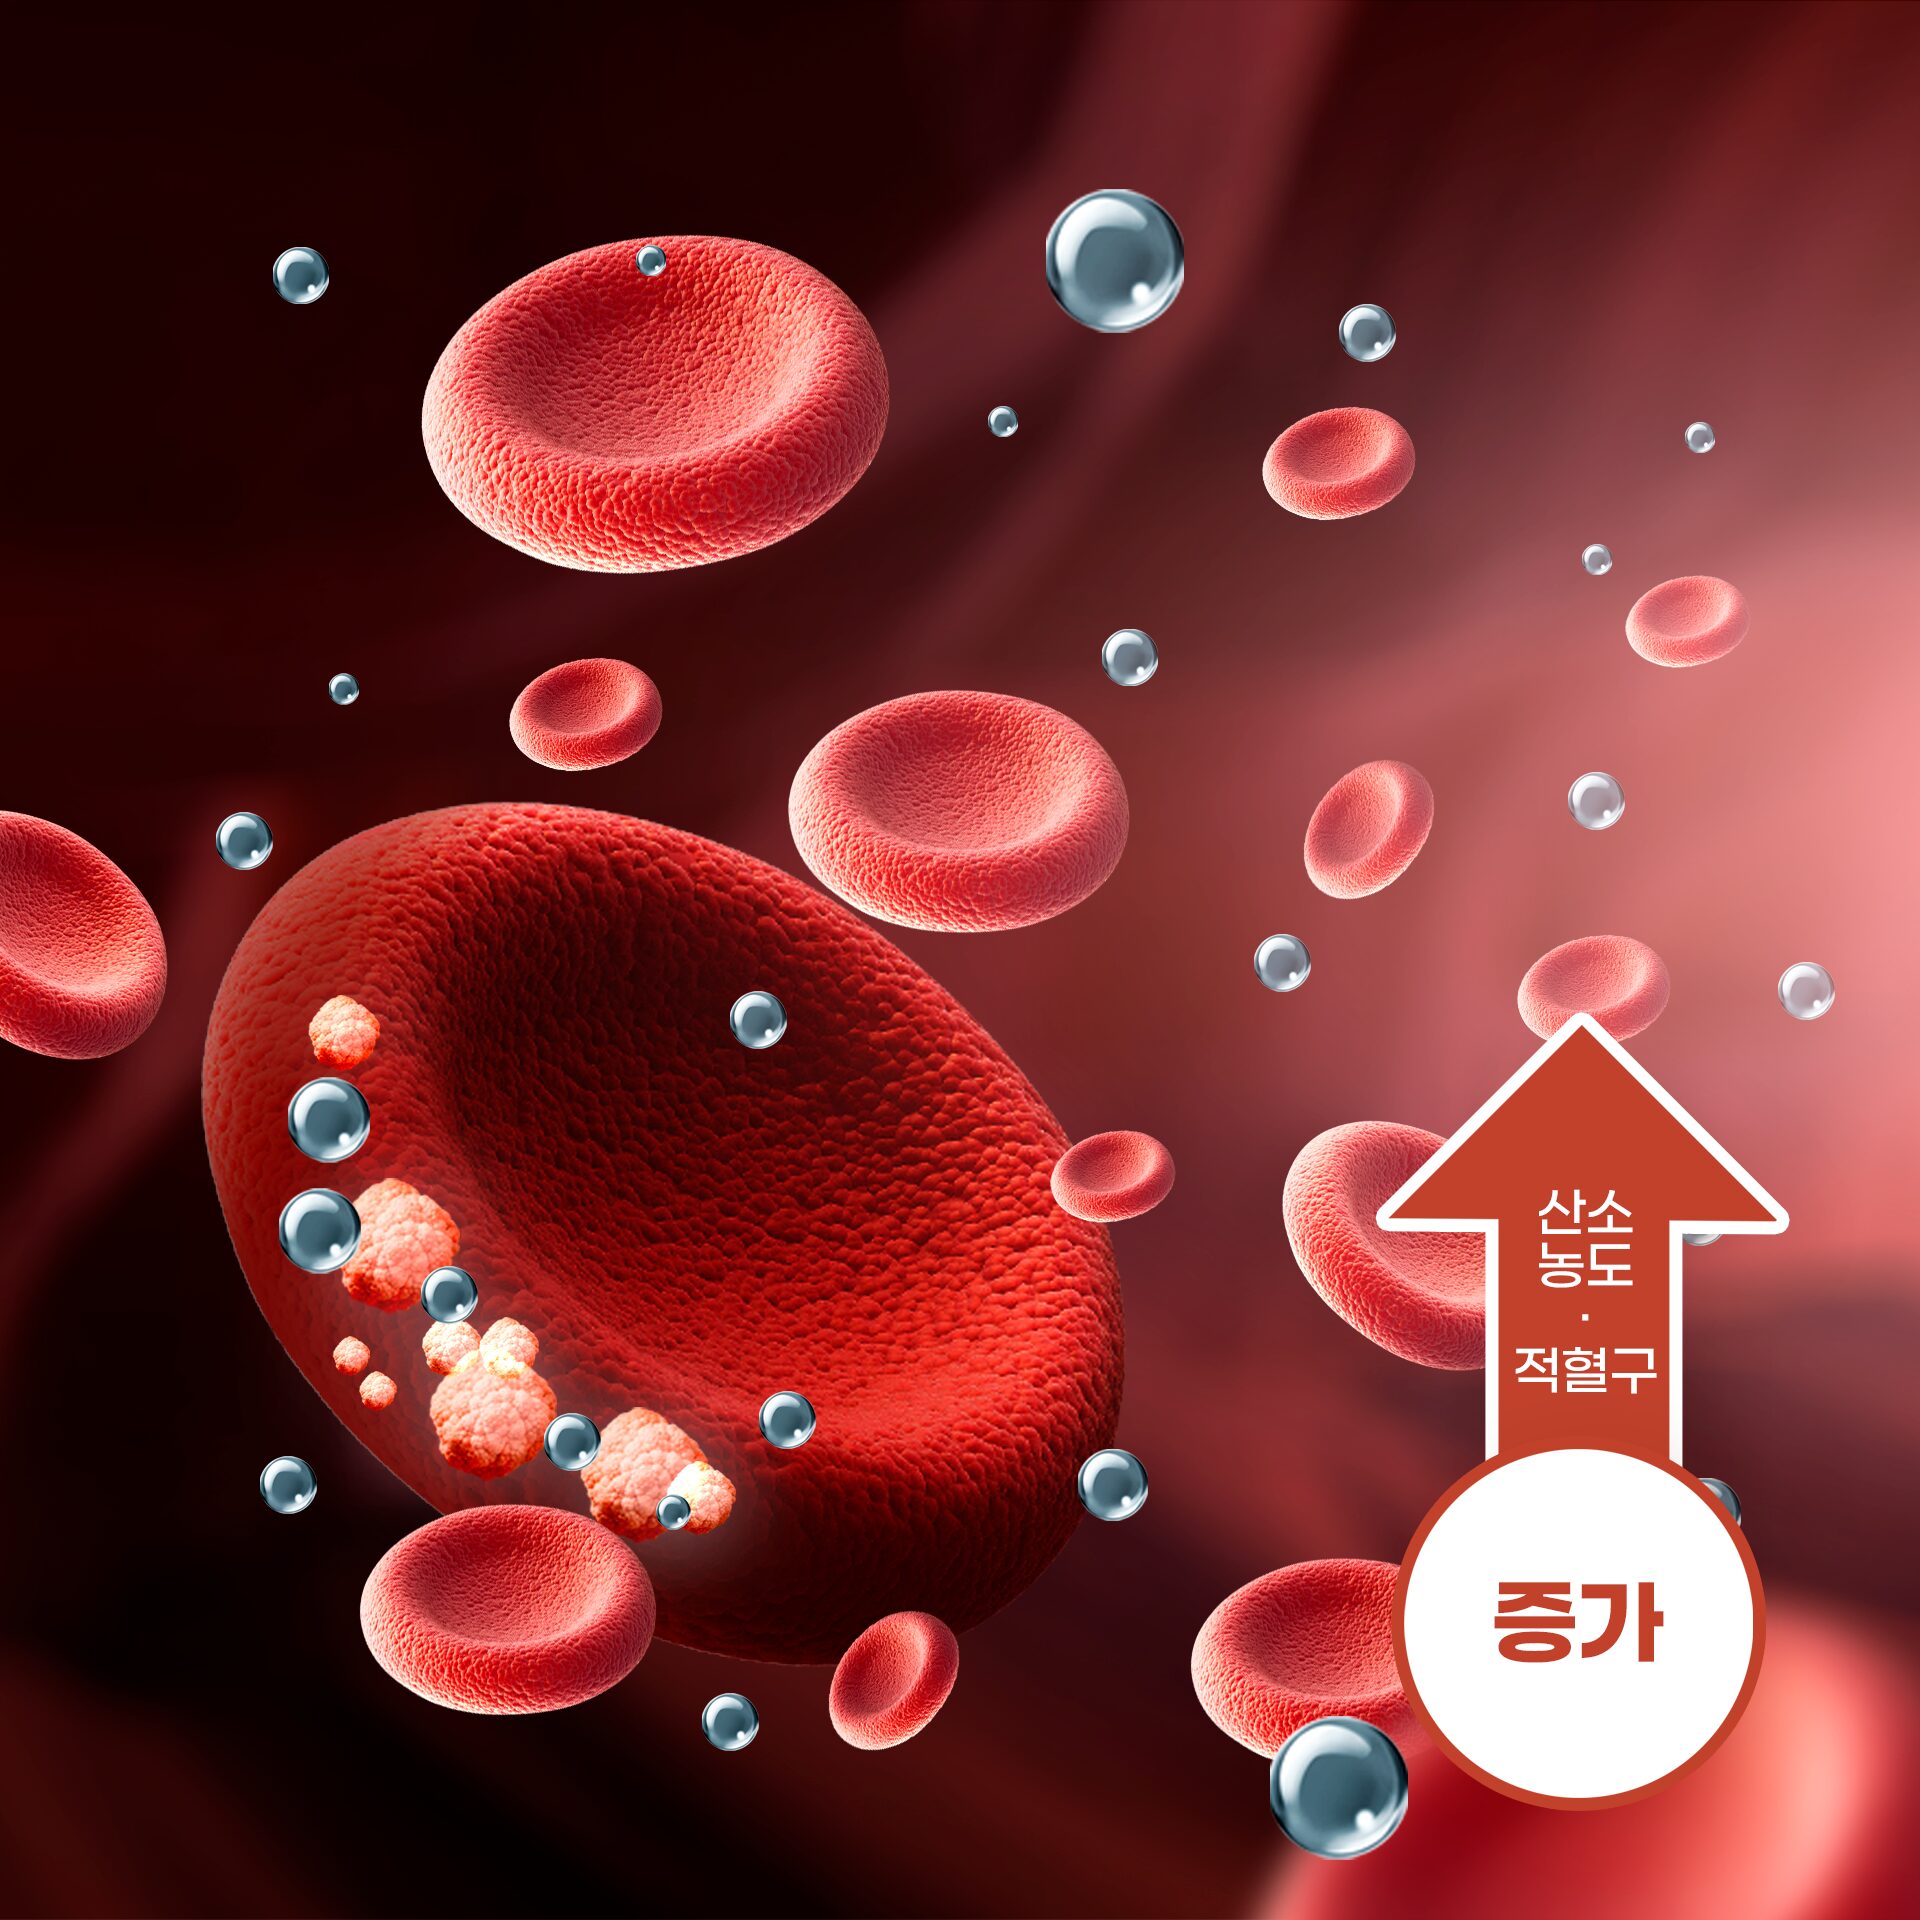

기존보다 2배의 산소가 혈액에 반응하여

손상된 조직이나 세포를 케어하는 최첨단 전신 항노화 치료 입니다.

고압산소

치료 목적과 효과

고압산소 치료는 미용 목적으로 많이 활용되고 있습니다.

주사 시술 후 고압산소 치료를 받으면 다운타임이 확연히 줄어듭니다.

피부 세포 재생 및 회복 촉진

고압 환경에서 고농도의 산소가 체내에 흡수되면 손상된 피부 세포의 재생을 활성화하고 새로운 세포 생성을 돕습니다.

고압 환경에서 고농도의 산소가 체내에 흡수되면 손상된 피부 세포의 재생을 활성화하고 새로운 세포 생성을 돕습니다.